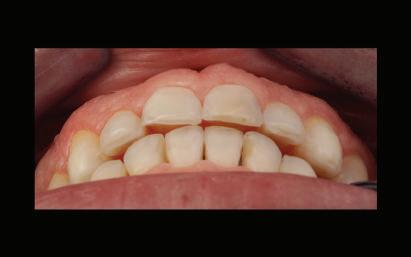

Dental Tribune Bulgarian Edition / октомври 2022 г.16 клиничен случай с алайнери Г орният латерален ре зец е вторият найчесто вродено липсващ зъб.1,2 Поради разполо жението му във видимата зона на усмивката лечение то на подобни случаи нала га мултидисциплинарен под ход, целящ отличен функцио нален и естетичен резултат. Налице са няколко лечебни мо далности, свързани с различ но разпределение на място то: първият вариант е орто донтско отваряне на място и възстановяване на липсва щия зъб с конструкция, под държана от съседните зъби3 или от имплант4, докато при втория подход разстоянията се затварят и премоларът заема мястото на канина.5 Изборът на лечебен подход трябва да бъде направен съв местно от зъболекар и паци ент въз основа на очакванията на последния и предвиди мостта на лечението. Множе ство фактори влияят върху това решение, като напри мер типа малоклузия, размера, формата и цвета на кучеш ките зъби6, оклузалните вза имоотношения (овърджет и овърбайт), лицевия профил, дължината на зъбната дъга и несъответствията в разме ра на зъбите.7 В настоящата публикация се разглежда случаят на жена в зряла възраст с вродена лип са на горен ляв латерален резец. Бяха приложени про зрачни алайнери за отваряне на място за единичен им плант и бяха постигна ти функционална оклузия и отлична естетика. ПРЕДСТАВЯНЕ НА СЛУЧАЯ Диагноза Пациентката бе на 32 годи ни, когато лечението започна, и първоначалното ѝ състоя ние бе следното (фиг. 1–3): липсващ горен ляв латерален резец; клас II, подклас I малоклузия; отклонение на горната сре динна линия вляво; Доклад на клиничен случай ЛЕЧЕНИЕ С АЛАЙНЕРИ НА ПАЦИЕНТ С АГЕНЕЗИЯ НА ЛАТЕРАЛЕН РЕЗЕЦ Д-р Iro Eleftheriadi и д-р Christodoulos Laspos, Гърция и Кипър Фиг. 1a–h Предоперативни лицеви и интраорални снимки. Фиг. 2a–e Дигитални модели преди началото на лечението. Фиг. 3 Панорамна снимка преди лечението. Фиг. 1a Фиг. 1d Фиг. 1f Фиг. 2a Фиг. 2d Фиг. 2b Фиг. 2e Фиг. 3 Фиг. 2c Фиг. 1b Фиг. 1e Фиг. 1g Фиг. 1h Фиг. 1c

Dental Tribune Bulgarian Edition / октомври 2022 г. 17клиничен случай с алайнери леко струпване в долната че люст; несъответствие по Болтън (мандибуларен излишък от 3.06 мм във фронталната зона и общо 1.47 мм); издължено лице с лицева аси метрия; конвексен профил с ретруди рана долна челюст и проми нентен нос. На мястото на зъб #46 бе на лице имплант, а зъби #16 и 26 са ендодонтски лекувани. Тези зъби бяха асимптоматич ни, затова бе взето решение да се прави релечение само при нужда. Мъдреците липсваха. Анализът на телерентгеногра фията (фиг. 4) показа ретрог натна мандибула (SNB: 74.2°) и нормална инклинация на резците както в